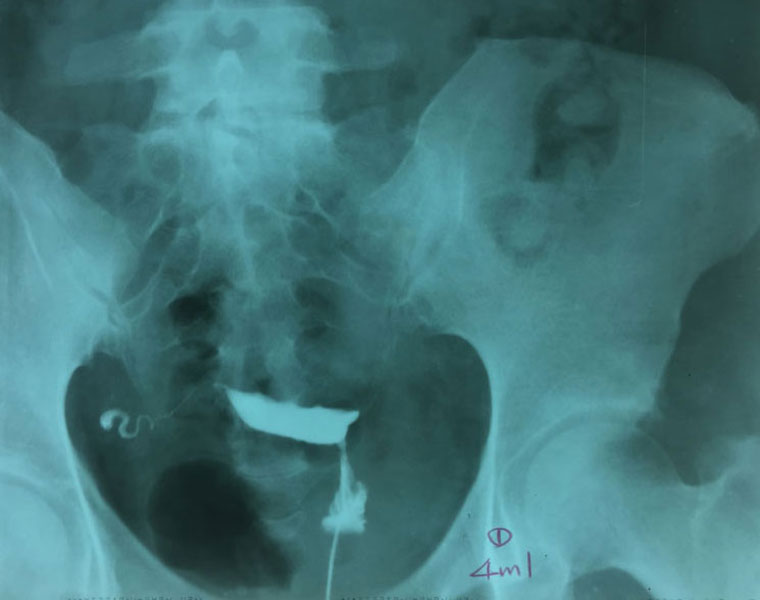

1. 注入顯影劑4ml

2. 注入顯影劑共8ml

3. 側位拍攝

4. 等待20分鐘後,兩側輸卵管均水腫